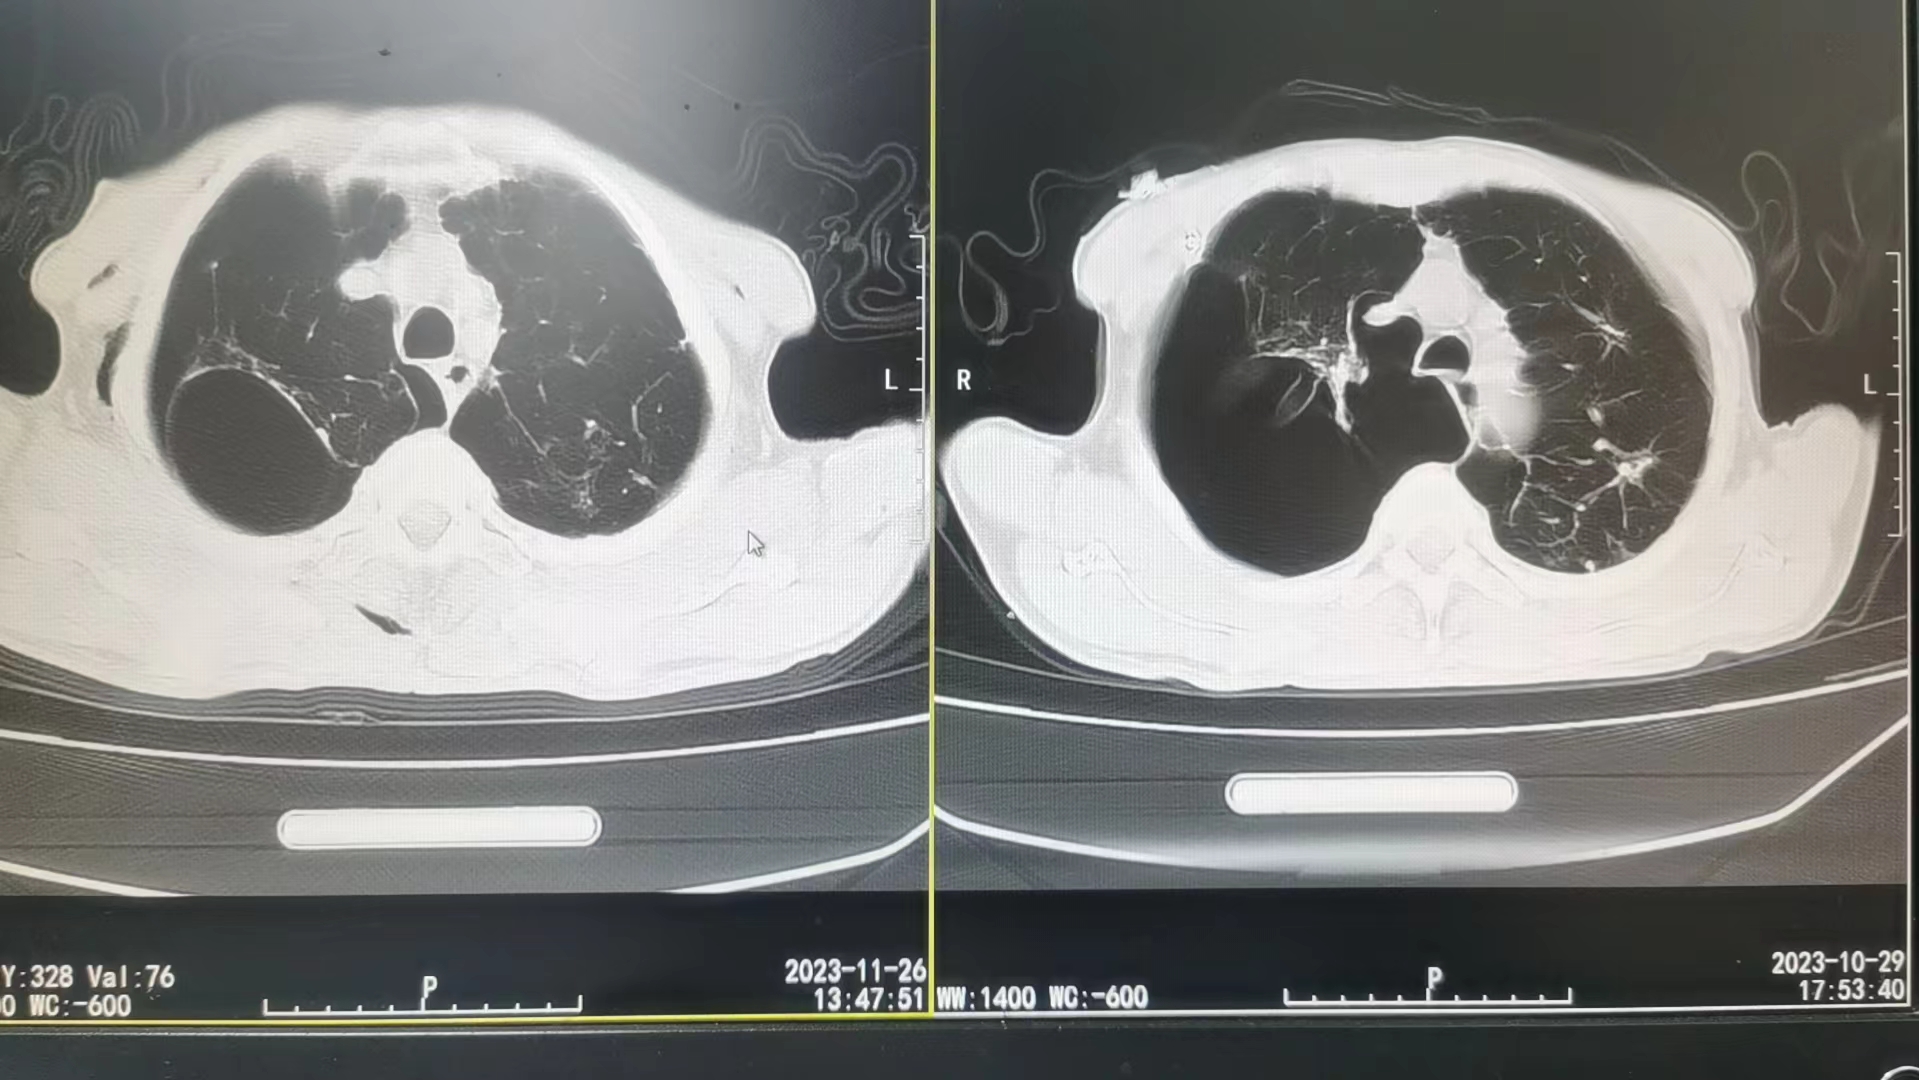

肺大泡治疗后(左)、治疗前(右)CT对比图

2023年秋,80岁的肖老因呼吸困难且行动不便被家人送至娄底市第二人民医院就诊,经检查发现,其肺部有巨大型肺大泡呈破裂状态,肺叶严重压缩是导致呼吸困难的主因。该院对肖老实施胸腔闭式引流和对症治疗,其症状得以缓解。但之后半个月,肖老的胸膜腔仍未闭合,气胸反复发作,肺部破溃口持续不愈合,后辗转多家大医院救治疗效欠佳,又回到娄底市第二人民医院保守治疗。彭瑶接诊后,针对肖老的病情查阅了大量的医学论文资料,最后决定采取胸膜固定术来帮助患者胸膜腔闭合。通过往患者胸腔闭式引流管内注入多西环素,使胸膜产生无菌性炎症而发生脏层和壁层胸膜相互粘连。经过1个月的精心治疗,取得突破性进展,让肖老摆脱了气胸的威胁。